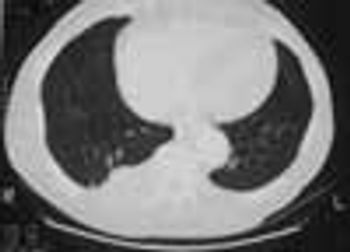

An 80-year-old man with a history of congestive heart failure, coronary artery disease, cardiomyopathy, and thoracic and abdominal aneurysms was taken to the emergency department because of mental status changes, back pain, and ecchymotic areas over his body. The ecchymoses started on his back 5 days before admission and spread to his abdomen.